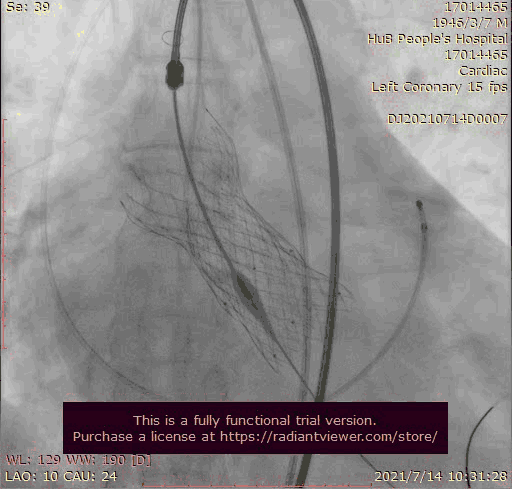

主动脉根部造影

输送器跨瓣

瓣膜稍高位释放

瓣膜位置稍深

使用venus-A plus回收后重新定位释放

瓣膜位置尚可

大结构瓣膜稳定性差,输送器使瓣膜跳到瓣上

奇思妙想使用射频消融大头压住支架至窦底

在大头压迫支架下释放第二个瓣膜

第二个支架完美释放固定第一个支架

术后基本无返流